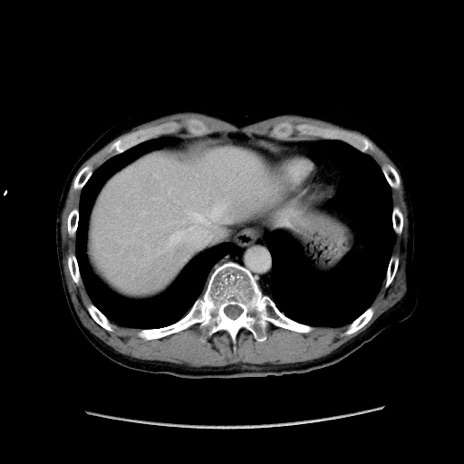

症例37(横断像)

【症例】40歳代 男性

【主訴】腹痛

【現病歴】4時間ほど前に電車に乗車中に臍部上より腹痛出現。徐々に増悪し起立困難となり、救急外来受診。生ものは数日食べていない。今朝お雑煮を食べた。

【身体所見】BT 36.8℃、BP 117/84mmHg、HR 91/min、SpO2 97%、苦悶様、腹部:臍上部広範囲圧痛あり、反跳痛±

【データ】WBC 8100、CRP 0.03